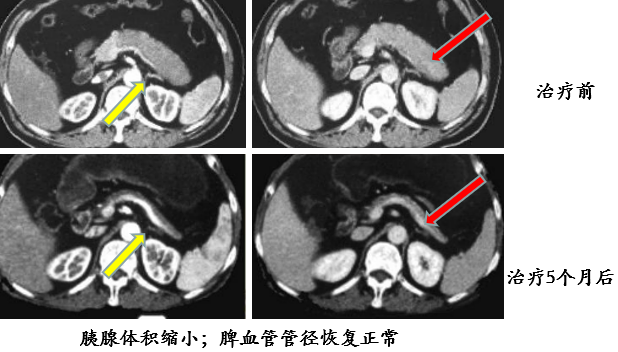

在影像学鉴别困难时,可结合类固醇激素实验性治疗,必要时结合血清学 IgG4 水平做出分析。

糖皮质激素治疗有效,能够使受累器官和组织恢复到原来的状态